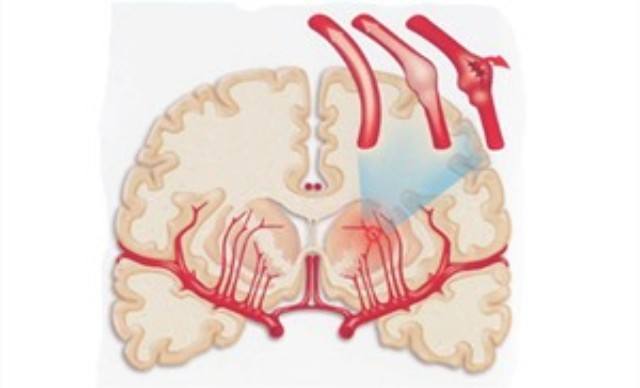

腦血管痙攣的病理圖

腦血管痙攣的位置漫畫

腦血管痙攣漫畫

引起腦血管痙攣病因